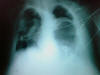

TBC pulmonar antigua